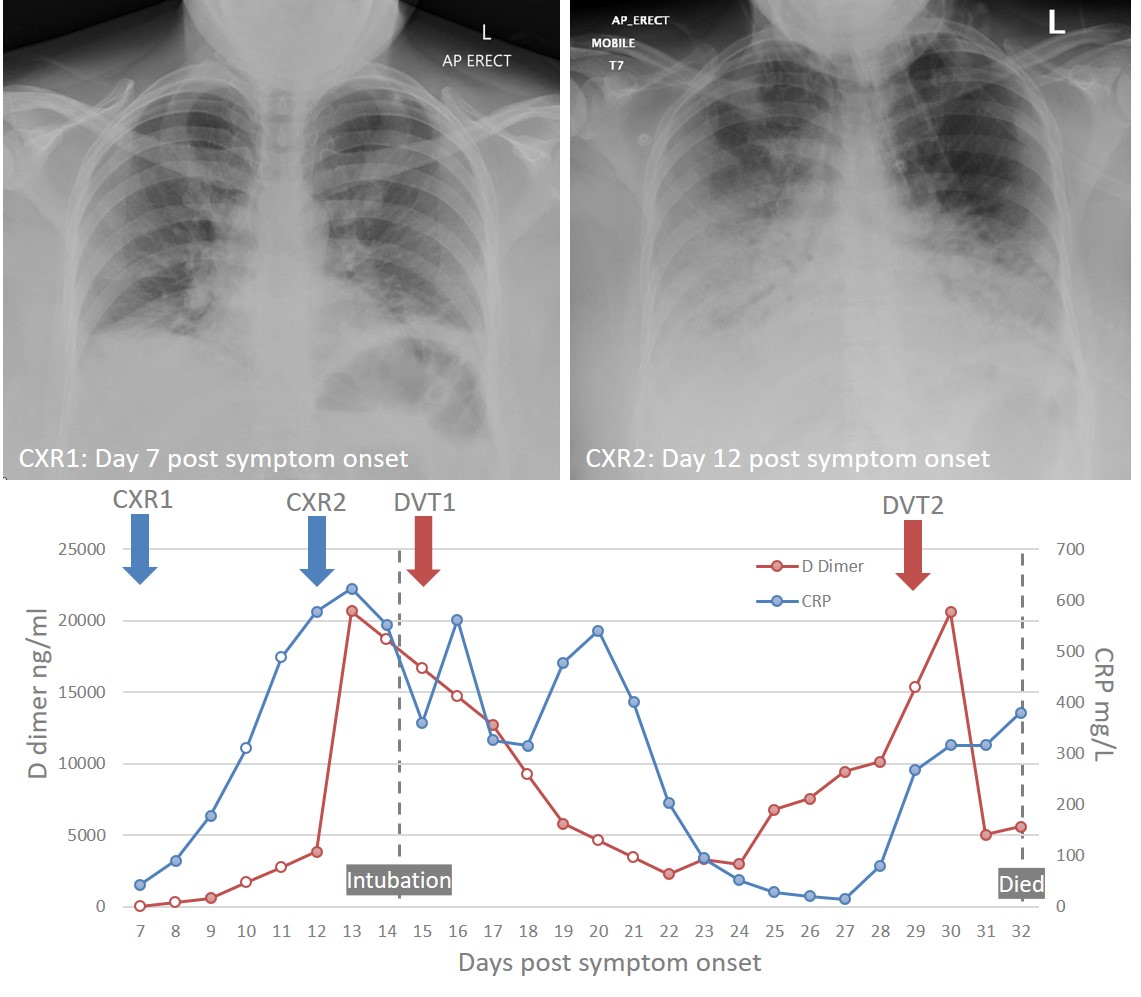

Our review on Emerging Immuno-Thrombotic Therapies for #COVID19 is now out in British Journal of Clinical Pharmacology (BJCP) Includes this clinical case illustrating the link between hyperinflammation and coagulation. MelanieJensen Derek Gilroy @ReechaSofat dx.doi.org/10.1111/bcp.14…

Our review on Emerging Immuno-Thrombotic Therapies for #COVID19 is now out in <a href="/BritJClinPharm/">British Journal of Clinical Pharmacology (BJCP)</a>

Includes this clinical case illustrating the link between hyperinflammation and coagulation. MelanieJensen <a href="/DerekGilroy1/">Derek Gilroy</a> @ReechaSofat